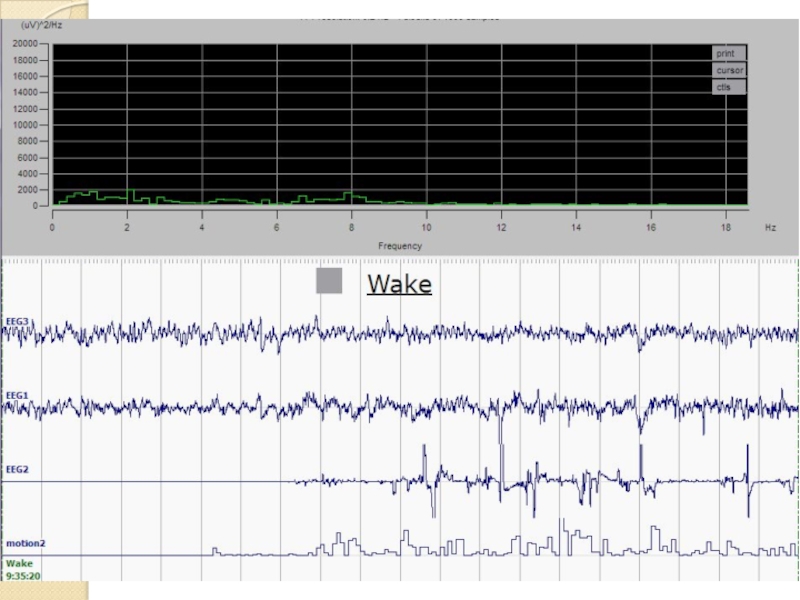

- 12. Стадирование сна по ЭЭГ Примеры записей ЭЭГ и движения Бодрствование Медленный сон Быстрый сон

- 13. Пример ЭЭГ бодрствования